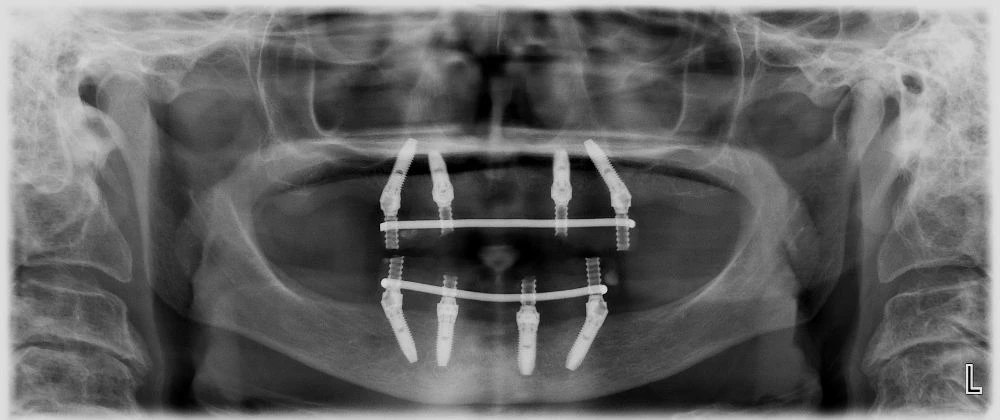

Лечение в долна и горна челюст с 4 специални тричастови, остеоинтегрирани зъбни импланта Nobel Speedy и неподвижен, винтово закрепен, сваляем мост от 12 зъба върху тях.

Същото лечение може да се проведе и с 6 импланта, когато има достатъчно обем кост в областта на 6-те зъби. При тази ситуация няма импланти, които да са поставени под ъгъл от 35 градуса.

Открити отвори 6 импланта Закрити отвори 6 импланта

Ето как изглеждат на RO графия зъбните мостове, завършени от пластмаса, металокерамика и цирконий.

RO пластмаса – Временната пластмасова конструкция не се вижда.

/зъбните импланти са поставени с хирургичен водач/

RO металокерамика – постоянна конструкция

/Вижда се слаба сянка около металния скелет. Това е порцеланът върху метала/

RO Цирконий – постоянна конструкция

/ Липсва слабата сянка на порцелана. Вижда се хомогенната сянка на Циркония/